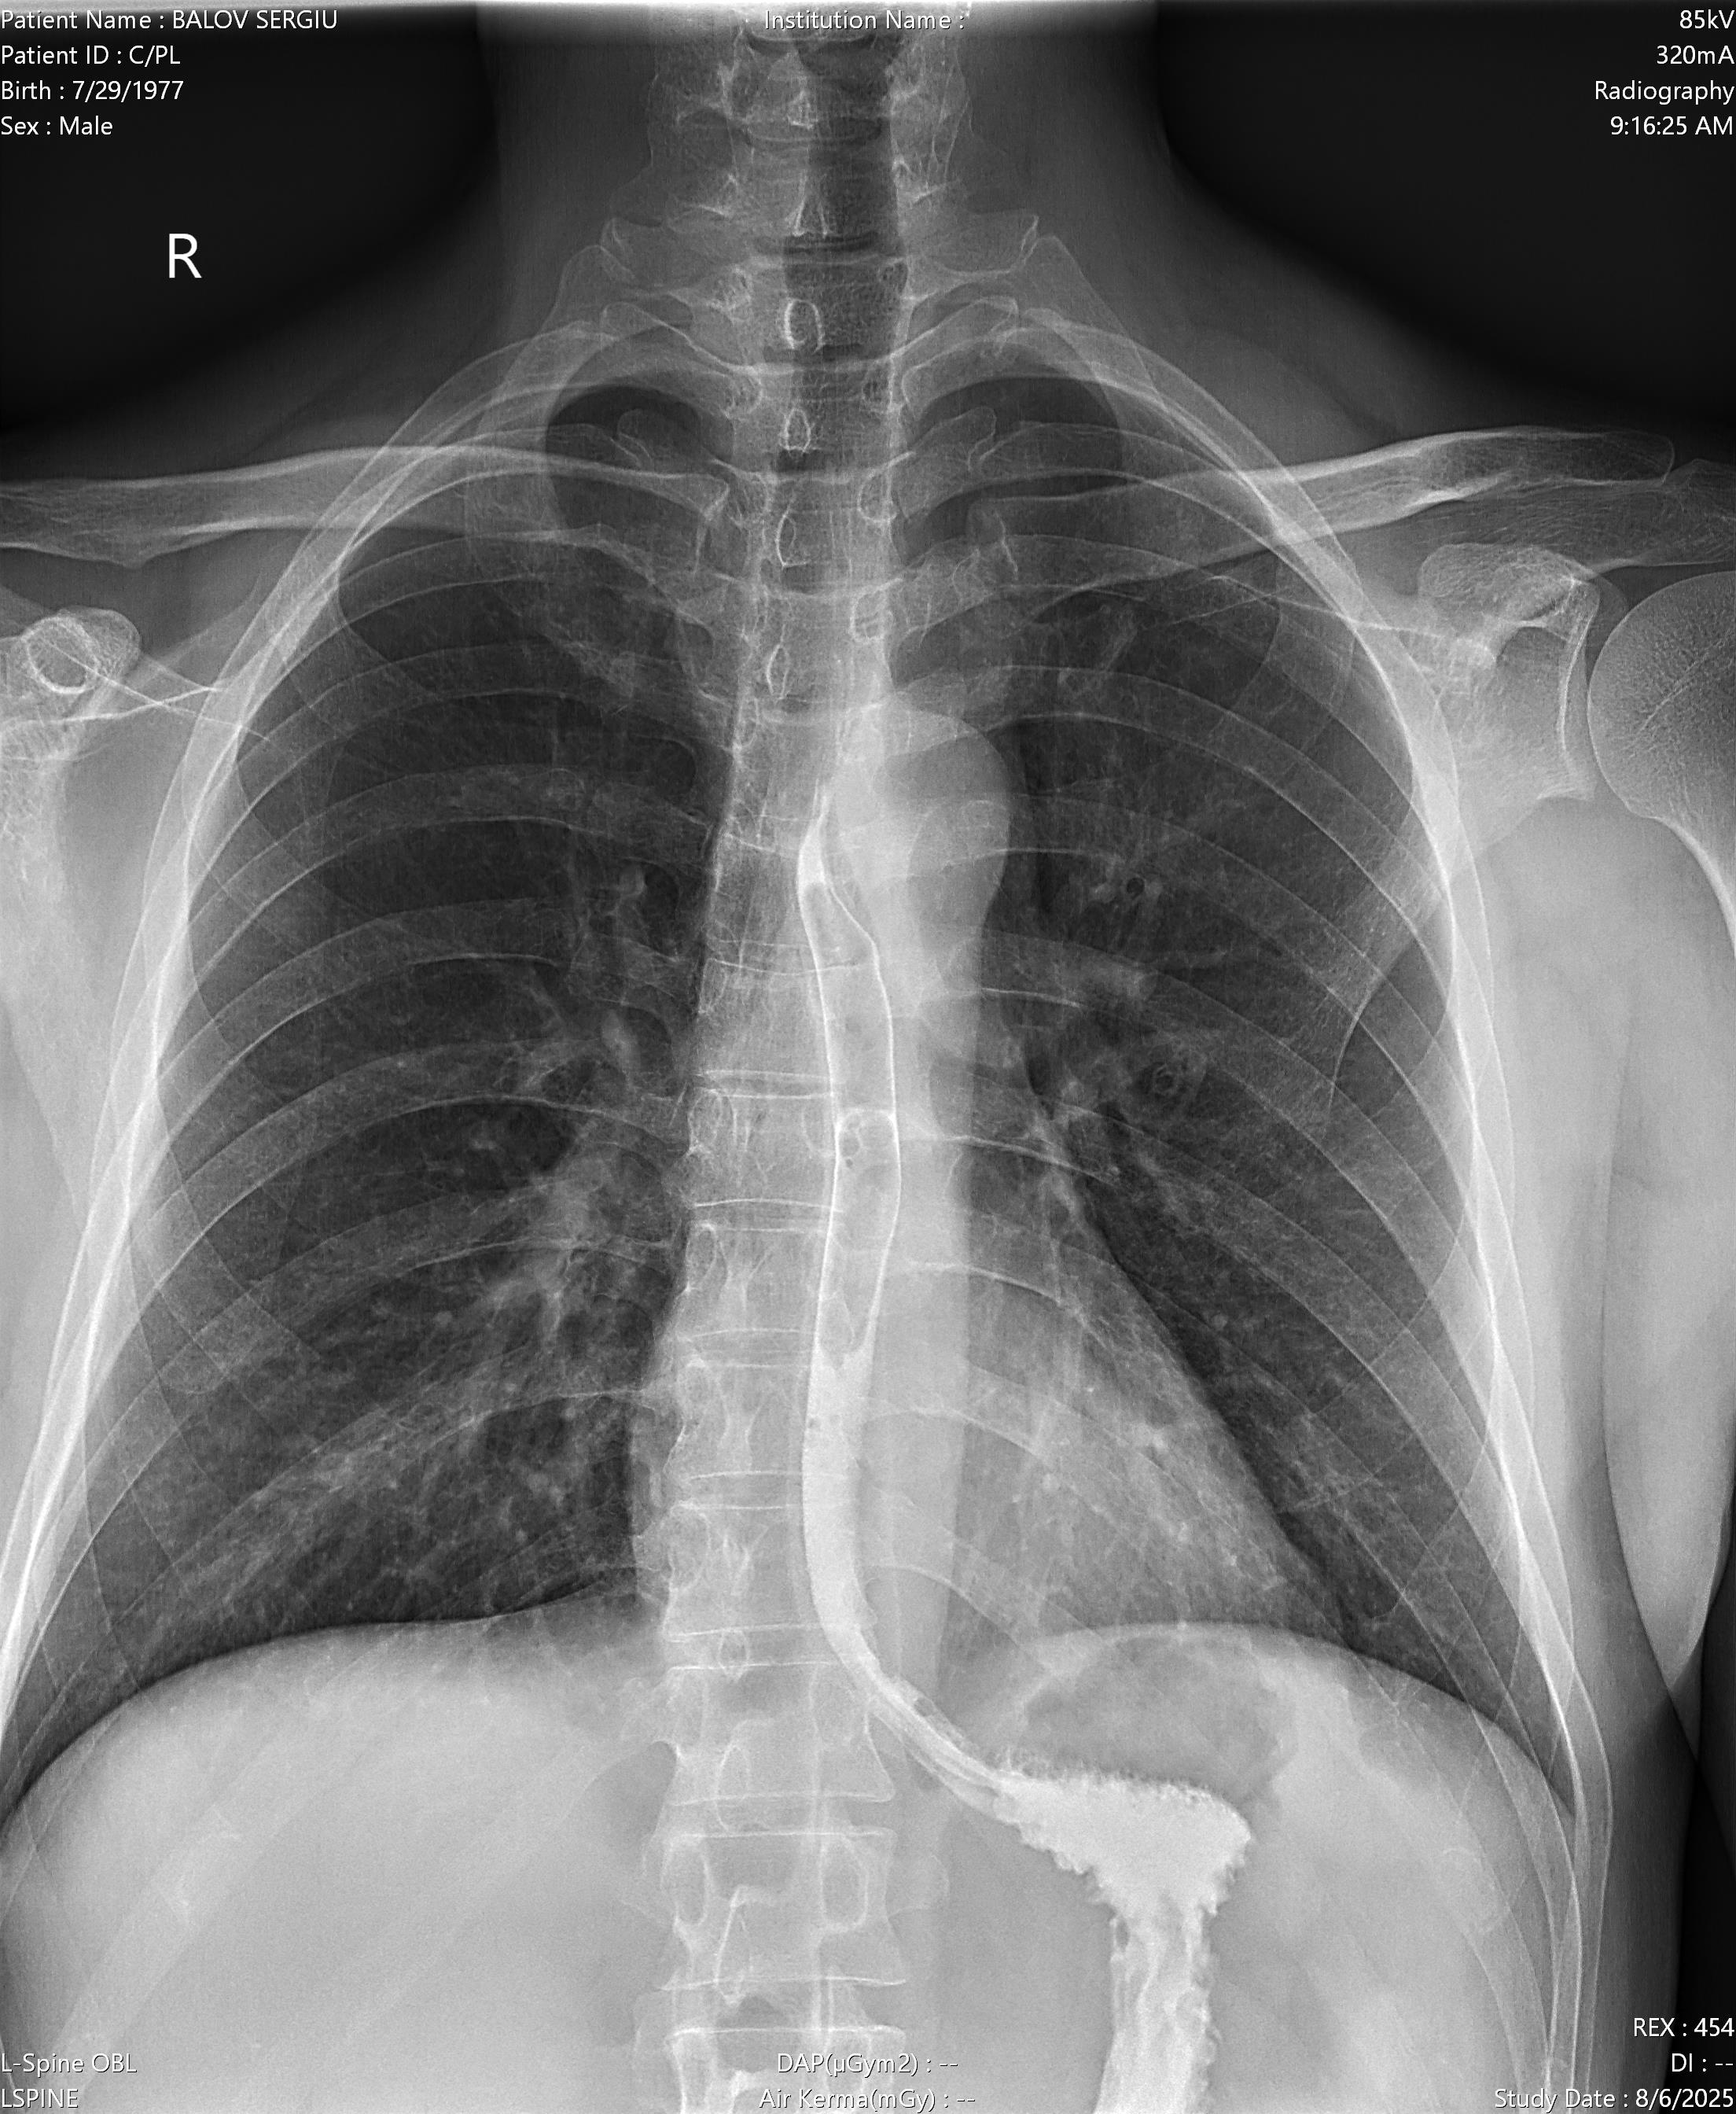

Здравствуйте!Визуализируется какая либо патология желудка(гэрб,грыжа,гастрит,язва и т.д.).За ранее спасибо!